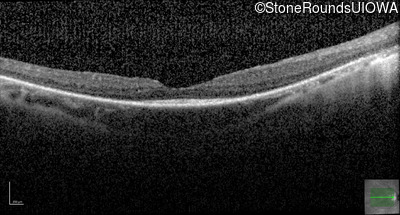

Optical Coherence Tomography - Right - 20/40 +1

Exemplar / OCT Stack